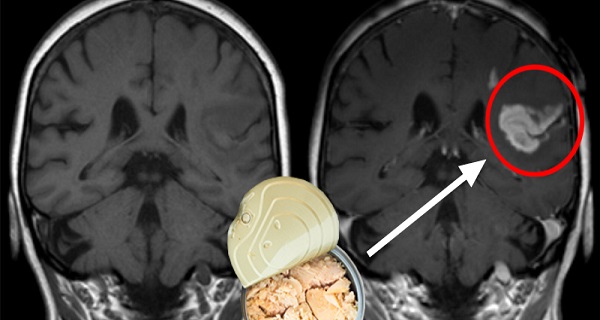

Домашний лакто-ферментированный лук для балансировки уровня кислоты в желудке, сжигания жиров и улучшения функций мозга